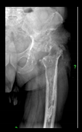

The radiological examination allowed us to verify the close bone-to-implant contact and the unchanged position of the implant during follow-up.

In all the cases operated with the above-described targeting procedure, the stems of the cups remained between the cortical bone surfaces without perforation of the linea terminalis, as shown by postoperative radiographs. There were no complicated surgical situations. In 16 cases, the wound healings were uneventful, and the hips were able to bear weight again after postoperative rehabilitation.